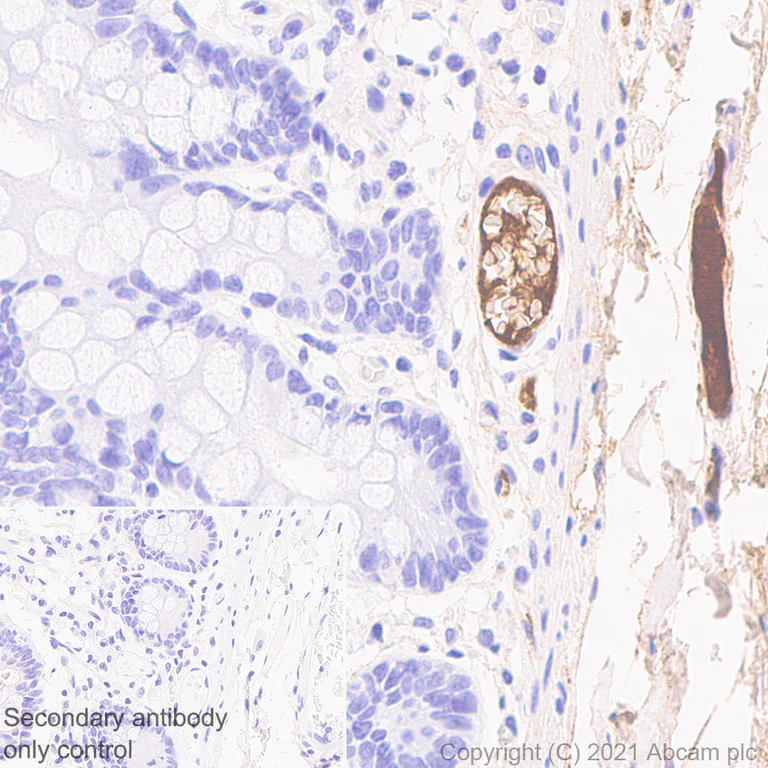

Immunohistochemistry (Formalin/PFA-fixed paraffin-embedded sections) - Goat Anti-Mouse IgG H&L (HRP polymer) (AB214879)

Immunohistochemical analysis of paraffin-embedded human colon tissue labeling MUC2 with ab11197 at 1/5000 dilution followed by a ready to use Goat Anti-Mouse IgG H&L (HRP polymer) (ab214879). The section was incubated with ab11197 for 30 mins at room temperature. The immunostaining was performed on a Leica Biosystems BOND® RX instrument. Counterstained with hematoxylin.